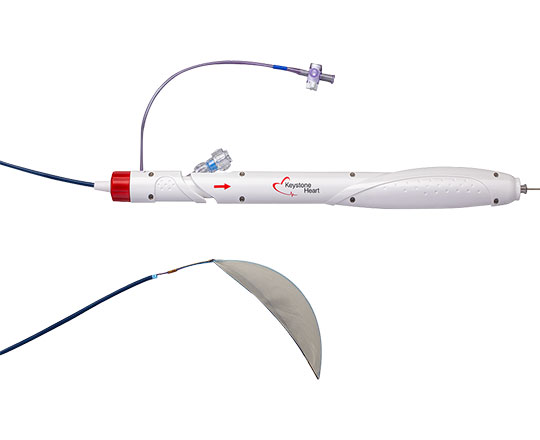

Balón de valvuloplastia True Flow

True Flow (Bard, EEUU) es un balón de valvuloplastia que permite el flujo a su través mientras está inflado. Su recubrimiento exterior está compuesto por un tejido de fibras que evita el deslizamiento del balón al abrirse sobre los velos valvulares, por lo que no se necesita estimular el corazón con marcapasos. Este tejido esta formado por poliuretano de alto peso molecular, poliéster y fibras de aramida (componente estructural del Kevlar) que posee una baja distensibilidad y alta resistencia a la rotura. El interior del balón tiene 8 globos de pequeño diámetro en el perímetro del balón principal, y deja un espacio entre ellos por donde fluye la sangre. El dispositivo mide 3,5 cm de largo y está disponible en seis tamaños, con diámetros que van de los 18 a los 26 mm. Los más pequeños son compatibles con un introductor de 11 French y el más grande con introductor de 16 French.